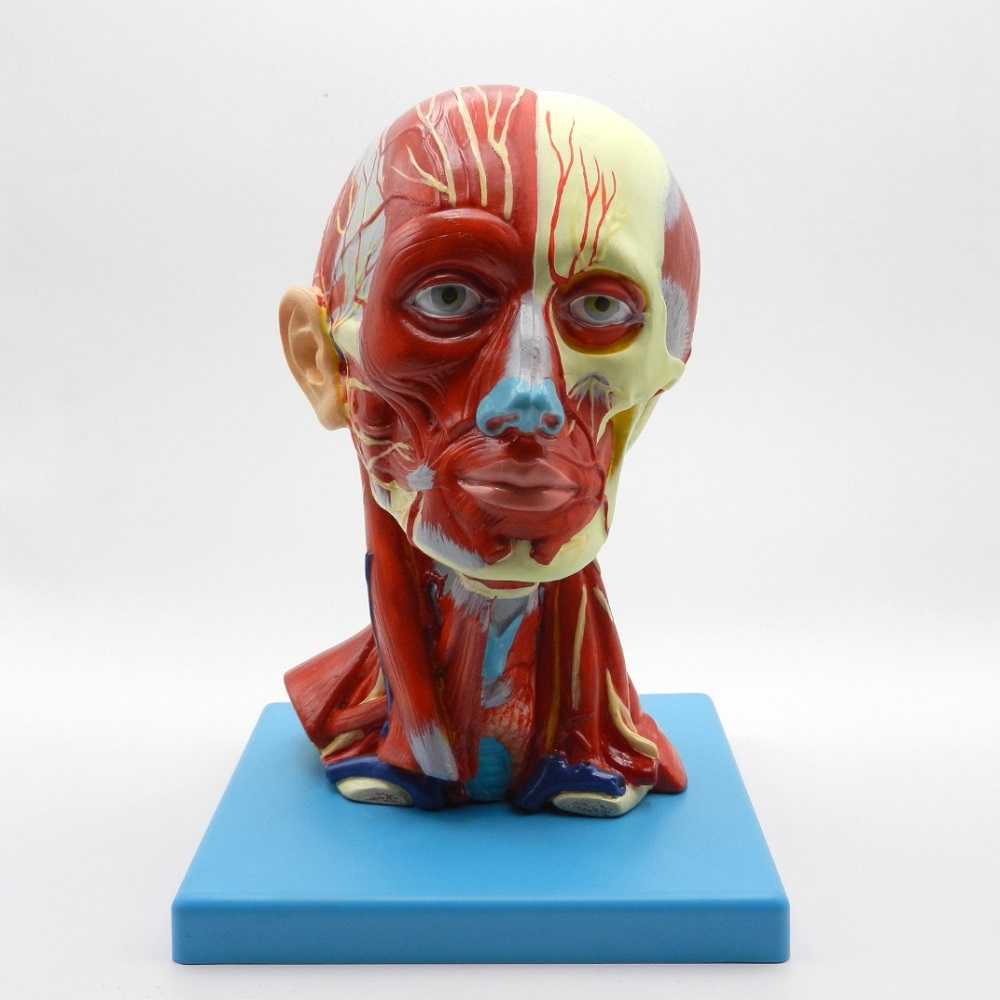

مولاژ کلمه ای فرانسوی به معنای قالب است. آناتومی بدن انسان با تجهیزاتی مانند مولاژهای پزشکی یا کالبدشناسی که نمونه هایی تخصصی و شبیه به اندام های بدن انسان هستند، به دانش آموزان و دانشجویان آموزش داده می شود. استفاده از مولاژ در روند یادگیری و آموزش تاثیر به سزایی داشته و تمامی اندام ها را با تمامی جزئیات و با کیفیت بالا می توان مشاهده و بررسی کرد. مولاژها عموما از جنس PVC نشکن، لاستیک یا فوم ساخته شده و دارای رنگ طبیعی و قابل شست و شو هستند. برخی از انواع مولاژها مناسب برای آموزش مراقبت های پزشکی و پرستاری است و امکان تمرین بانداژ، تزریق، CPR، جراحی و... وجود دارد. مولاژها معمولا هر کدام عضوی از بدن را نمایش می دهند و قابلیت تفکیک و مشاهده همه بخش های آن وجود دارد.

مولاژها معمولا با توجه به نوع اعضا و یا دستگاه های بدن در اندازه طبیعی، کوچکتر و یا چندین برابر بزرگتر ساخته می شوند تا امکان مشاهده دقیق اجزای آن ها فراهم شود. برخی مولاژها از چندین قطعه ساخته شده اند که قابلیت تفکیک دارند. علاوه بر نمایش ساختار و نحوه عملکرد اعضای بدن، ماهیچه ها و عضلات بدن را نیز می توان به کمک مولاژها مشاهده کرد.

مولاژها ابزاری تخصصی برای آموزش دانشجویان پزشکی، دندان پزشکی، پرستاری و مامایی است. همچنین در مدارس و سایر مراکز آموزشی میتوان از انواع مولاژها برای بهبود یادگیری و آموزش بهره برد. در کلینیک های زنان و زایمان، دندان پزشکی، سالن های تشریح، بیمارستان ها و آزمایشگاه ها نیز مولاژهای مراحل حاملگی، انواع دندان و بیماری های آن کاربرد دارند.